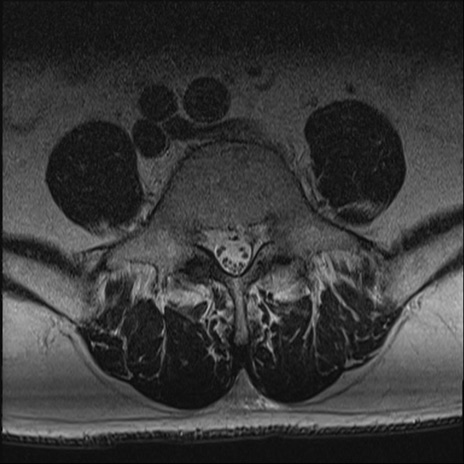

【整形】TIPS症例2 腰椎MRI T2WI(横断像)

【症例】70歳代男性

【主訴】左下肢痛

【現病歴】2週間前くらいから腰痛、左下肢痛あり。左臀部から大腿、下腿外側のしびれが常時ある。歩行とともに同部位の痛みあり。

【身体所見】Lasegue70-/60+、Bragard-/±、PTR ±/±、ATR -/-、IP 5/5、TA 5/4、TS 5/5、EHL 右第1足趾なし/3、FHL 5/5、hypersthesia(-)、足背動脈触知良好

異常所見と診断は?